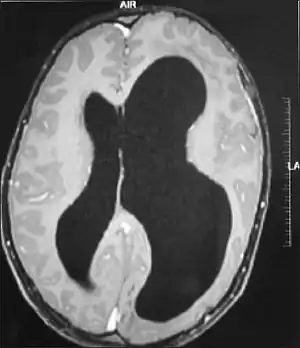

| An MRI of a patient with benign familial macrocephaly (male with head circumference > 60 cm) | |

Macrocephaly is a condition in which circumference of the human head is abnormally large.[1] It may be pathological or harmless, and can be a familial genetic characteristic. People diagnosed with macrocephaly will receive further medical tests to determine whether the syndrome is accompanied by particular disorders. Those with benign or familial macrocephaly are considered to have megalencephaly.

Benign or familial macrocephaly

Benign macrocephaly can occur without reason or be inherited by one or both parents (in which it is considered benign familial macrocephaly and is considered megalencephaly form of macrocephaly). Diagnoses for familial macrocephaly is determined by measuring the head circumference of both parents and comparing it to the child's. Benign and familial macrocephaly is not associated with neurological disorders.[2] While benign and familial macrocephaly does not result in neurological disorders, neurodevelopment will still be assessed.